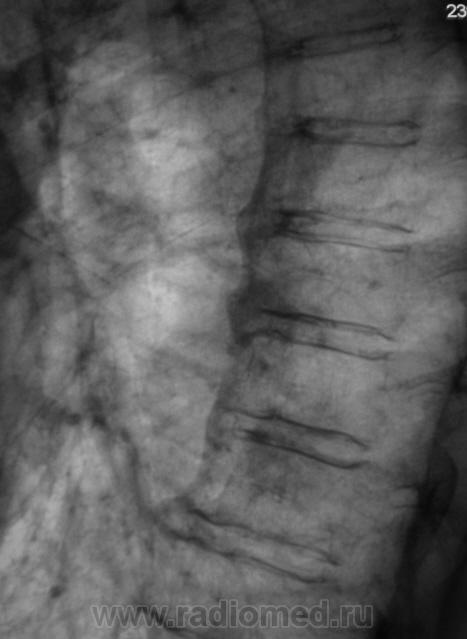

Контроль после флюорографии. Стандартное дообследование.

Ваше мнение уважаемые коллеги?

Mts? Но откуда? Что в анамнезе?